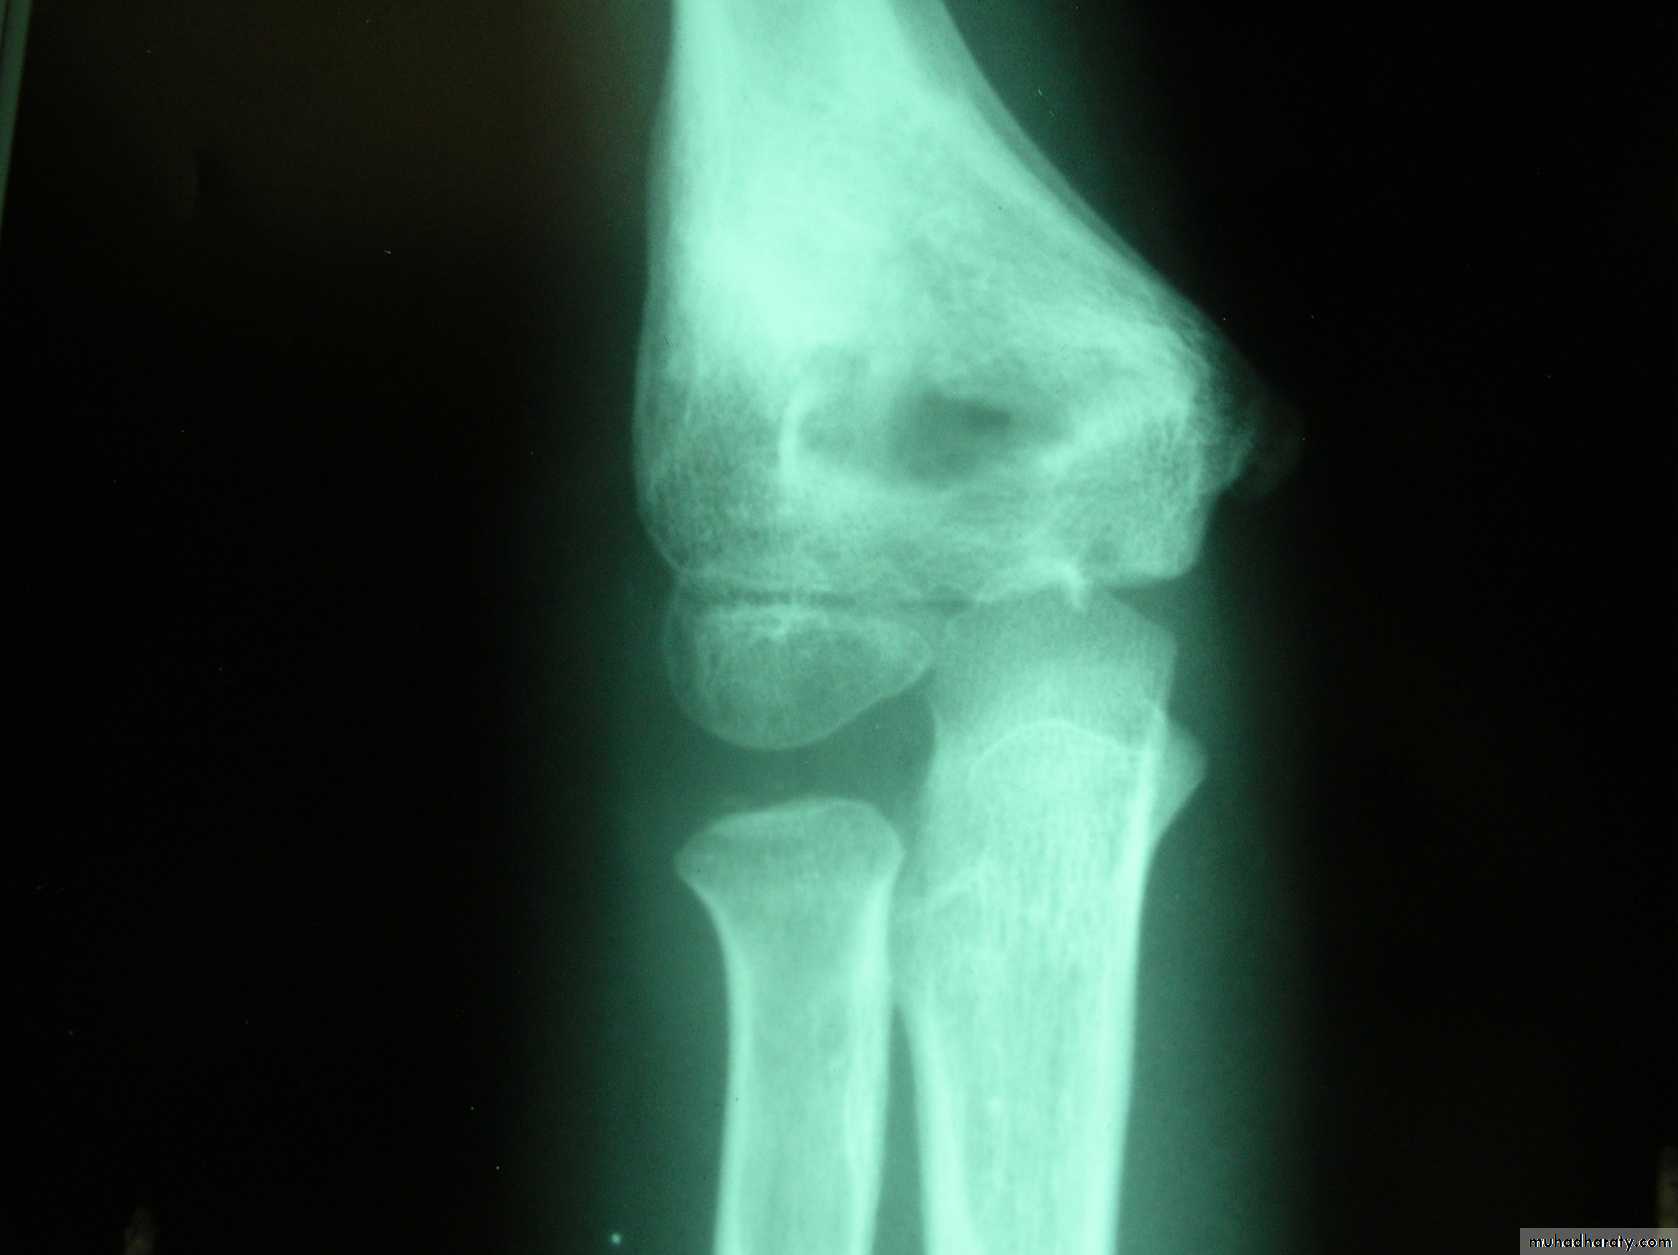

What type of supracondylar fracture

does this patient have?Flex

ionHow do the flexion patterns present?

This classical Type III pattern

This also is a Type III Flexion Pattern.

What is differentabout this fracture?